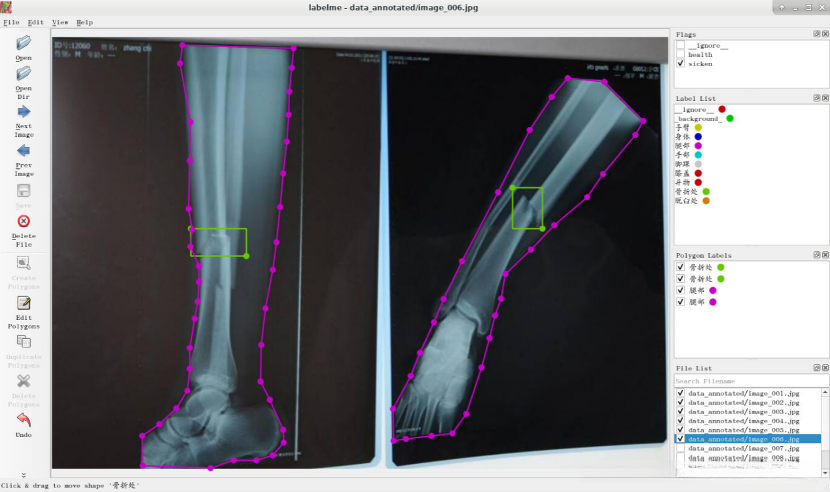

由于结果图片过多,仅展示部分图片。

任务实施过程

- 使用labelme进行图像标注

观察图像,判断患者是否健康,认为该患者是健康的,所以flag选择“health”。

请在电子图像中识别出人体关键部位,并通过右键点击执行"Create Polygons"操作。

左键点击图片,将图像中的手臂标注出来,选择相应的label,然后点击OK。

点击OK后,结果如下图所示。

10.点击“Next Image”,将图像中人是否是健康的,无法判定时选择“ignore ”。

将图像中人体标注出来并选择相应的label。

点击“Next Image”,判断健康状况并选择相应的flag。